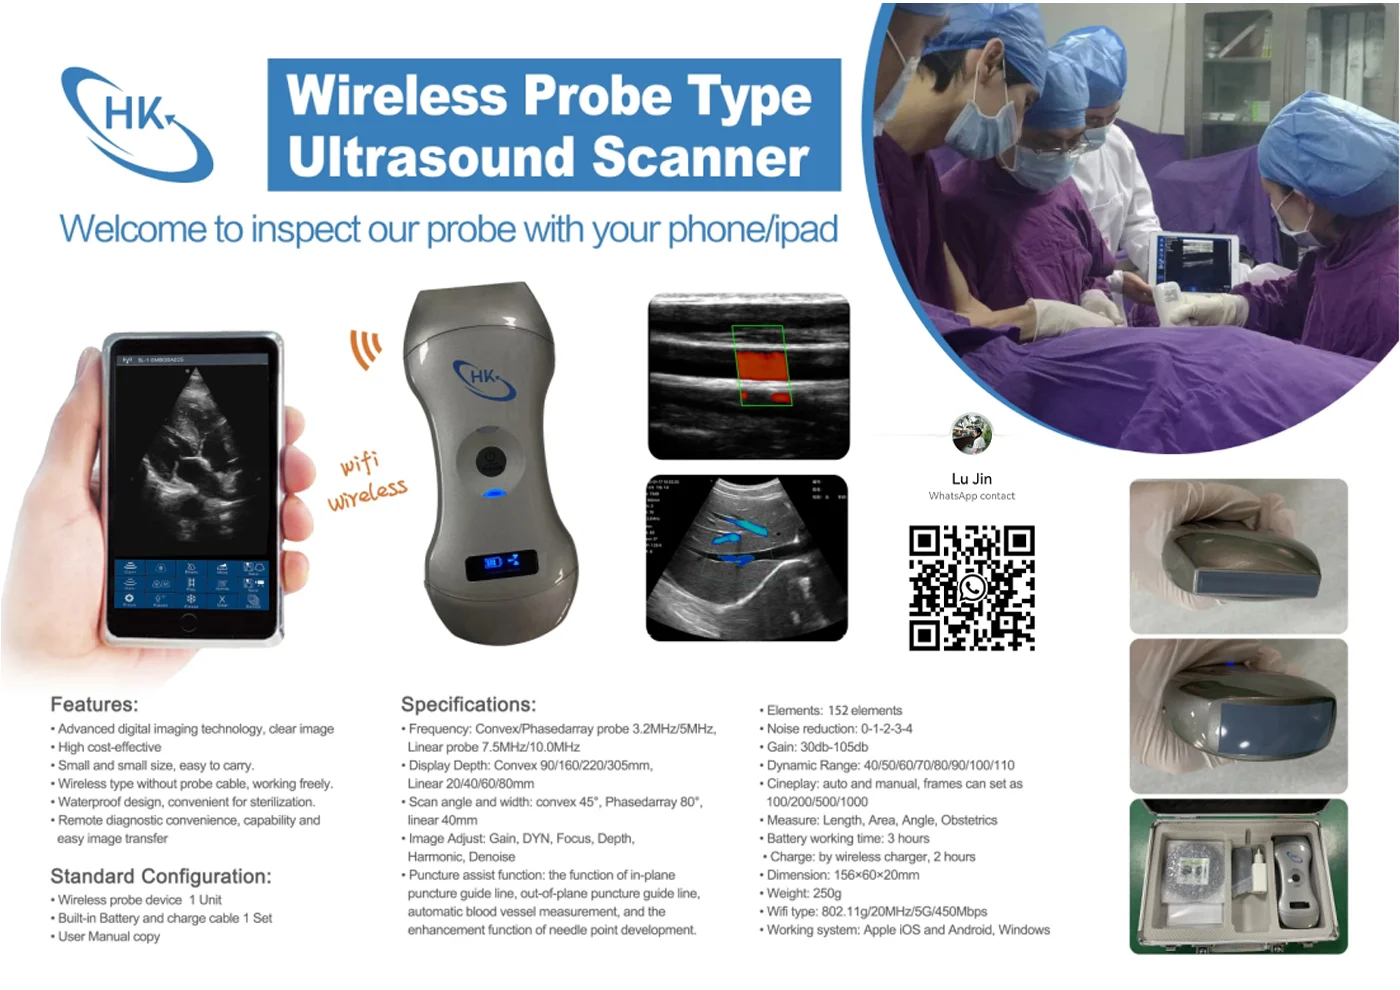

Small Full Digital Portable Ultrasound Equipment with Android/IOS Windows

Convex Probe Parameters

-Scanning system: array sweep

-Frequency: 3.5MHz

-Probe element: 80

-Depth: 90-200mm

-Host:

IOS: IPAD mini/IPAD air/IPHONE etc.

Android: Smartphone/pad, Samsung, HTC, Sony, Huawei, LG etc.

Windows: windows 10 system

-Connection: 802.11.g WIFI(AP)

-Throughout: 54Mbps

-Field of view: 80 degree

-Display mode: B,BM

-Image gray scale: 256 level

-Gain:30-105Db

-Measure: distance, area, obstetrics and other

GA(CRL),GA(BPD),GA(GS),GA(FL),GA(HC),GA(AC)

-Language: English, Russian, Italian, Spanish, Chinese, Portuguese

-Power: by built-in battery

-Power consumption: 10W (probe run) /2W (probe stop)

-Battery last: 3 hours

-Footprint: 156mmx60mmx24mm

-Weight: 308 g

Linear Probe Parameters

-Scanning mode: Electronic array

-Display mode: B, B/M

-Probe element: 80

-Channel of RF circuit board: 16

-Frequency: 7.5MHz/10MH

-Scan depth: 20/40/60/100mm

-Head width: 40mm

-Image Adjust: BGain, TGC, DYN, Focus, Depth, Harmonic, Denoise, Color Gain, Steer, PRF

-Cineplay: auto and manual, frames can set as 100/200/500/1000

-Puncture assist function: the function of in-plane puncture guide line, out-of-plane puncture guide line, automatic blood vessel measurement.

-Measure: Length, Area, Angle, heart rate, Obstetrics

-Image save: jpg, avi and DICOM format

-Image frame rate: 18 frames / second

-Battery working time: 3~5 hours(according to different probe and whether keep scan)

-Battery charge: by USB charge or wireless charge, take 2 hours

-Dimension: 156×60×20mm

-Weight: 220g~250g

-Wifi type: 802.11g/20MHz/5G/450Mbps

-Working system: Apple iOS and Android, Windows 10 system

Standard Configuration:

-Main Host(probe) 1 Unit

-Internal Battery and charger 1 Set

-Non-slip lanyard

Convex Probe Pictures:

Linear Probe Pictures: